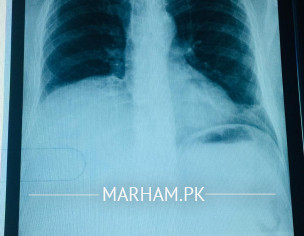

Assalamualaikum, In 1996 my father was diagnosed with multiple HH's we followed up regularly (u/s abdomen) every year till 2018 the large one is in right lobe which increases but not that rapid. as we consulted with Dr Abdal Waseem at siut in 2021 he said no intervention is needed he had also said this in 2015 and back in 2015 Dr jahanzaib At NILGID (Dow hospital Ojha campus) suggested embolization and surgery but we were satisfied with Dr Abdal's opinion. for second opinion today we went to Dr Rizwan Khan at AKUH he said largest hemangioma's size is 22cms i want to know what actual size of hemangioma's are and what can further we do in this regard. queries 1) What options are available now? 2) Size of largest hemangioma? 3) For further investigation and prognosis where we should go? 4) Is it necessary to intervien? at this stage Jazakallah PS he has following diseases now he is complaining of SOB in attaching his reports and X-rays as well. HTN ,DM , Hypothyroidism, BPH ,GERD. attach

as x-ray shows it is compressing the lung so it needs intervention

but before this we need to check haemangio in other organs like lung , intestine I would say full body